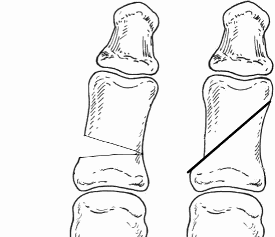

The aim of the surgery is to realign the first metatarsal almost parallel to the second metatarsal. This will move the big toe back into a straight position. This is achieved by cutting the bone. Sometimes re-balancing the soft tissue around the joint or taking a small wedge of bone out of the big toe is also required (Akin). The outcome of your operation will be dependent on the quality of your joint, the degree of arthritis present. There are numerous operations to correct bunions, but essentially, they fall into two categories: transposition and rotational procedures. Transposition osteotomies include the ‘Scarf’ and the ‘capital’. Rotational procedures include the ‘Lapidus’.

A transposition osteotomy such as a Scarf or capital osteotomy is where the bone is cut and moved across. The amount of correction available is restricted by the width of the bone. It is ideally suited to moderate deformities. In severe cases a rotational procedure such as a ‘Lapidus’ is preferred. Here a greater degree of correction is available. This operation also takes longer to heal and to settle down. Either procedure may be combined with an ‘Akin’ to help move the big toe to a straight position.

This is an osteotomy in the metatarsal head (transposition), the metatarsal head is moved to correct the deformity and fixated with a single screw. It is indicated for mild to moderate deformities. The choice to carry out a Scarf or a capital osteotomy will be made by your consultant.

This is a transposition osteotomy. It is normally indicated for mild to moderate deformities. The new position of the first metatarsal is maintained with two screws which enables stability.